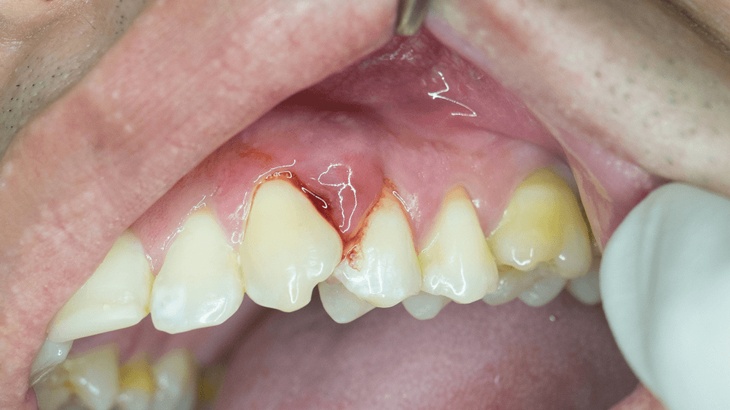

Áp xe nướu răng là một dạng nhiễm trùng xuất phát từ biến chứng của sâu răng hoặc nứt răng do tác động mạnh từ bên ngoài. Những tình trạng này dẫn đến sự xâm nhập của vi khuẩn sâu vào tủy răng, gây ra nhiều biến chứng, trong đó nổi bật nhất là chết tủy.

Áp xe xảy ra khi có sự tích tụ mủ tại vị trí bị viêm dưới mép nướu, tạo thành túi mủ. Nếu túi áp xe nướu không được phát hiện và điều trị kịp thời, có thể dẫn đến nguy cơ vỡ túi mủ, gây ra nhiễm trùng nặng nề, hủy hoại cấu trúc xương hàm, răng và các mô mềm trong miệng.